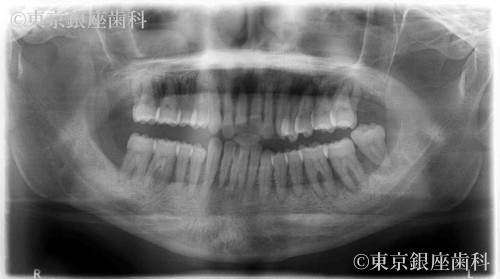

何年間も歯科医院には通っておらず、全ての歯の揺れがひどく今にも抜けそうだったが金銭的な理由により一時保留にしていた。3年後に来院した際には、歯周病が悪化し著しい歯の揺れ、骨の吸収が見られた。そして左上の前歯が自然脱落した。

歯周病の進行により歯に動揺があり長期の保存が難しくこのままでは予後が不安であった為全顎的な治療が必要と判断。上下全ての歯を抜歯。重度の歯周病により骨が吸収されているため、上顎骨が薄く左側は上顎洞に骨を足す治療(サイナスリフト)を行い上顎に4本、下顎に4本のインプラントを埋入しワンデイインプラントを行った。現在半年メンテナンス。